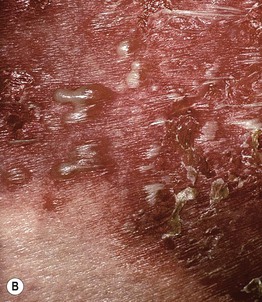

Fig. 6.9 Annular pustular psoriasis. Multiple annular inflammatory plaques studded with pustules. As the lesions enlarge, there can be central clearing, dry desquamation (A), and/or moist desquamation that resembles wet cigarette paper (B). B, Courtesy, Peter C. M. van de Kerkhof, MD.

– Significant overlap with AGEP.